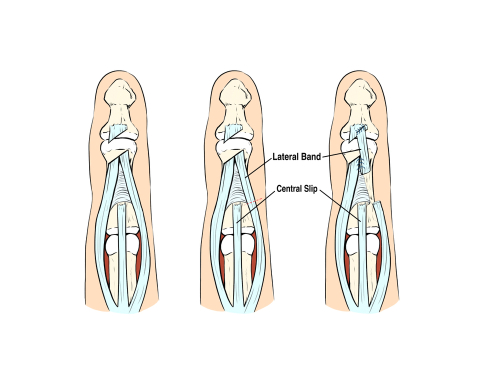

相对运动矫形器与动态伸展矫形器相比,哪种矫形器设计更适合 5-6 区伸肌腱损伤?

M. Buhler, ˝ D. Gwynne-Jones, M. Chin 等人,(2023) 与动态伸展相比,相对运动伸展矫形器的结果是否非劣质且具有成本效益......

文章评论:伸肌腱修复区 V-VI 的相对运动?夜间休息手部矫形器有用吗?

Hirth, MJ、Hunt, I.、Briody, K.、Milner, Z.、Sleep, K.、Chu, A.、Donovan, E. 和 O'Brien, L. (2021)。两种相对运动延伸的比较...

一项比较早期主动运动计划的随机临床试验:早期手部功能、TAM 以及对 V 区和 VI 区伸肌腱修复的相对运动延伸计划的矫形器满意度

作者:Brittany Day Collocott SJ、Kelly E、Foster M、Myhr H、Wang A、Ellis RF。一项比较早期主动运动计划的随机临床试验:早期......